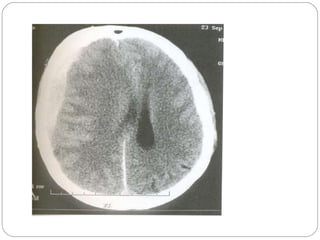

Investigations CT Scan with Contrast  MRI with Contrast Except cerebral abscess  Technetium brain scan – destructive skull vault, skull base lesions EEG – Cerebral abscess, focal slow waves seen Skull Film- not useful in hemispherical tumors Routine tests  Angiography, volumetric MRI Lumbarpuncture only after imaging  Biopsy

Investigations CT Scanwith Contrast MRI with Contrast Except cerebral abscess Technetium brain scan – destructive skull vault, skull base lesions EEG – Cerebral abscess, focal slow waves seen Skull Film- not useful in hemispherical tumors Routine tests Angiography, volumetric MRI Lumbarpuncture only after imaging Biopsy